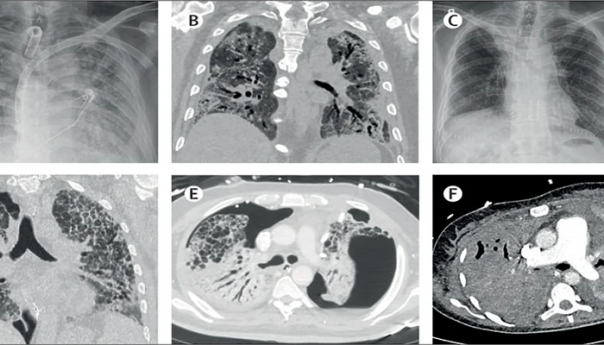

Za transplantaciju moraju biti ispunjeni kriteriji: iscrpljenost svih konzervativnih opcija terapije, izostanak oporavka pluća oštećenih Covid- 19 unatoč četverosedmičnoj terapiji podrške disanju putem ECMO (izvantjelesna membranska oksigenacija) aparata, potvrda o uznapredovalom i nepovratnom oštećenju oba plućna krila u nekoliko uzastopnih pregleda CT aparatom, starost ispod 65 godina i nepostojanje relevantnih popratnih oboljenja.